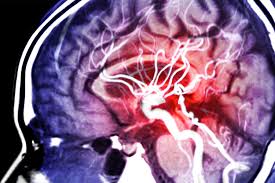

뇌의 혈관에 문제가 있으면 3시간 이내에 병원에 도착하는 것이 급선무입니다.

막힌 혈관을 뚫른 등 특별한 조치가 반드시 필요합니다.

뇌출혈, 뇌경색, 뇌졸중 등 무서운 질환으로부터 건강한 뇌를 지켜내는 것이 건강의 지름길이 아닐까 하는 생각이 듭니다.